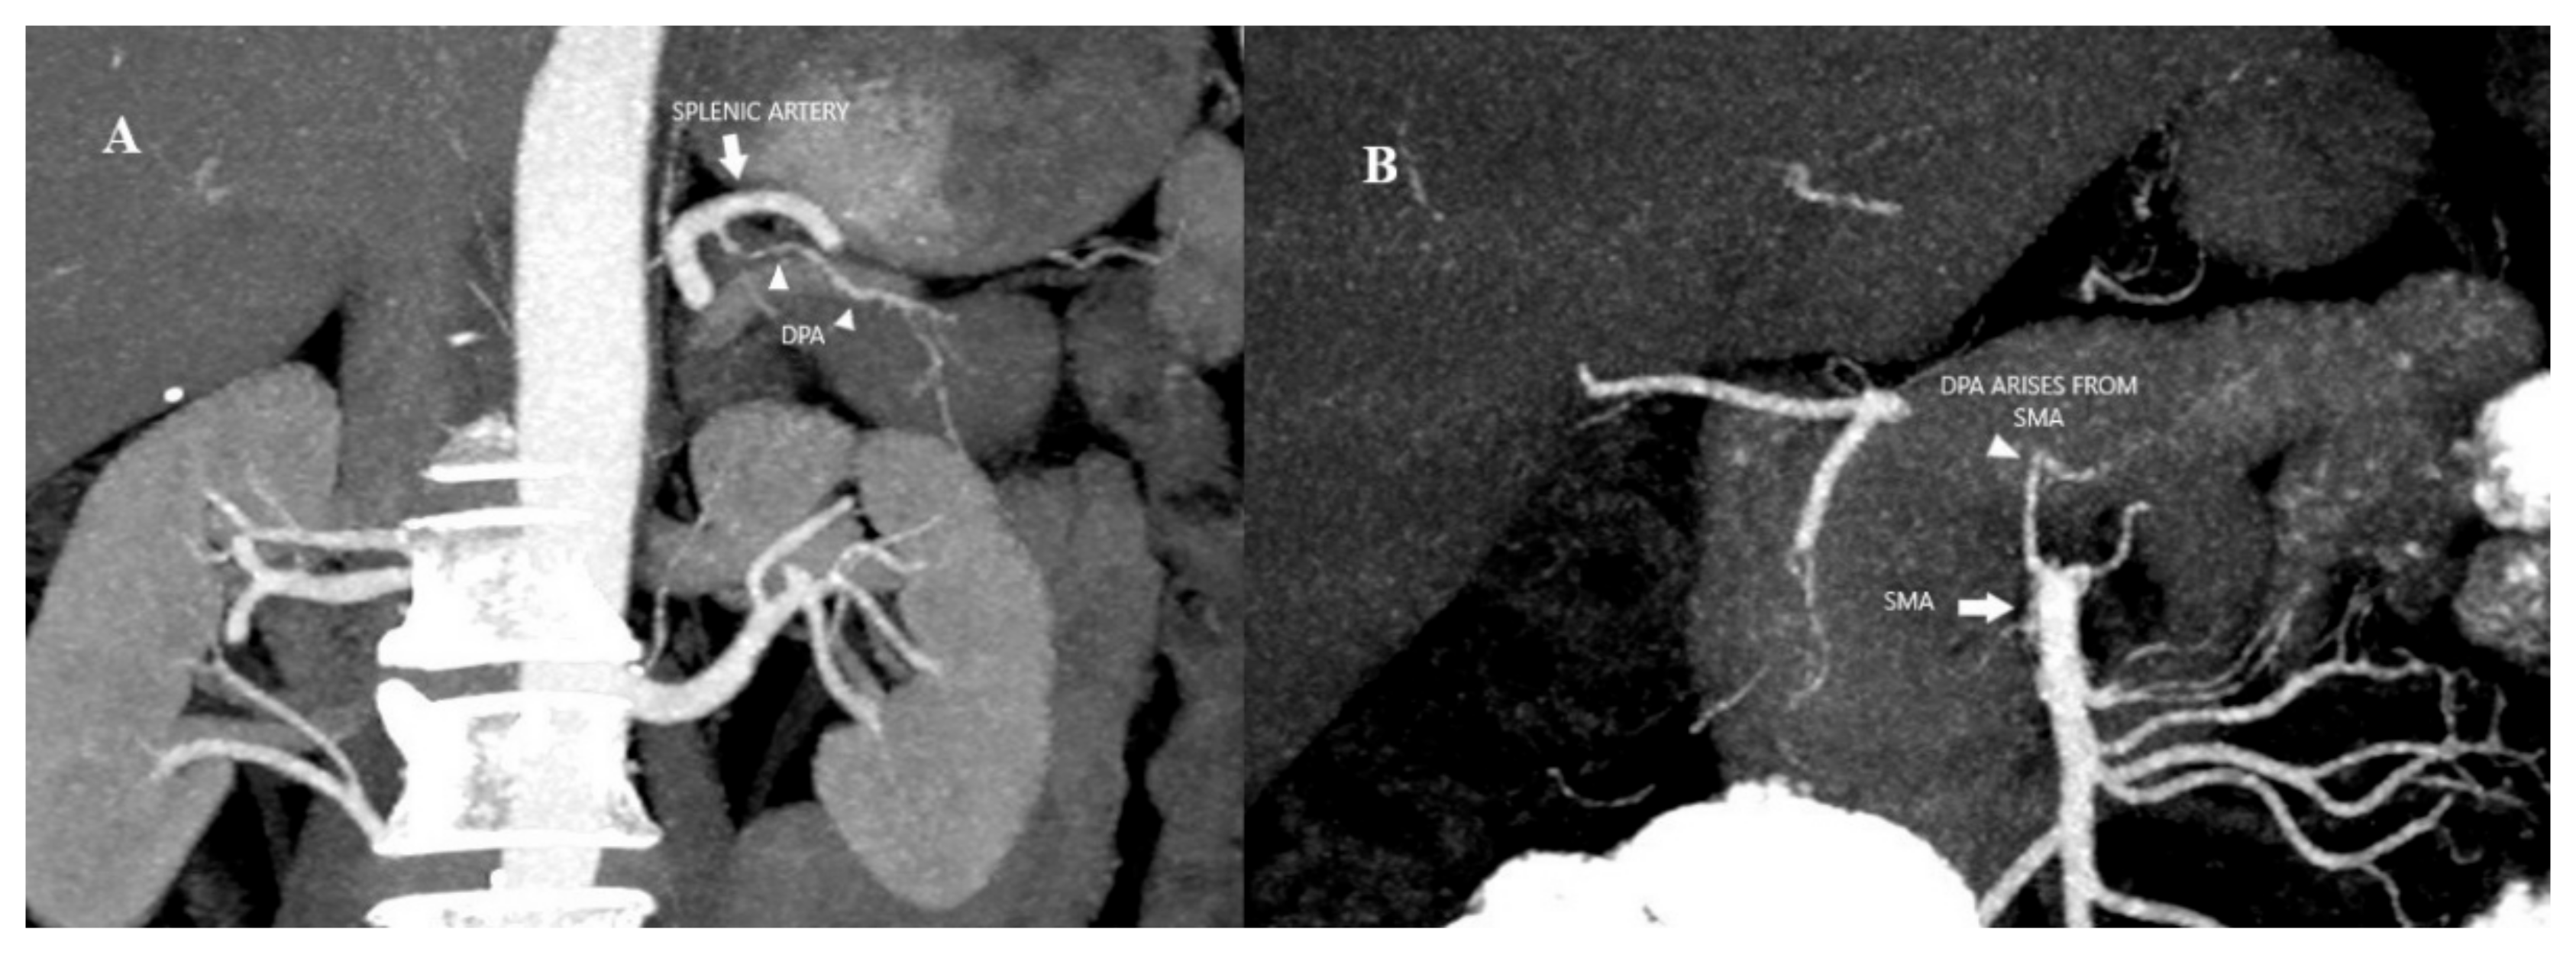

Readers were tasked with assessing the following variables: (a) origin of the DPA and (b) intrapancreatic arcade classification type. The origin of the DPA was evaluated (Figure 1). Previously, the anatomy of the intrapancreatic arcade has been categorized into four types: type 1 (minor arcades), type 2 (minor and major arcades), type 3 (major arcades) and type 4 (straight branches) according to Roman Ramos et al. [18]. The intrapancreatic arcade anatomy was grouped according to this classification (Figure 2)

Figure 1.

(A) Coronal MIP image of arterial phase of CECT abdomen shows DPA (arrowhead) arising from splenic artery (arrow). (B) Coronal MIP image of arterial phase of CECT abdomen shows DPA (arrowhead) arising from superior mesenteric artery (arrow).

According to the origin distribution of DPA, SA was the most common origin in 69.2% (n = 110) of the patients, the other origins were common hepatic artery (CHA) 4.4% (n = 7), gastroduodenal artery 3.8% (n = 6), SMA 17.6% (n = 28), celiac artery 3.8% (n = 6), dual SA–gastroduodenal arteries 0.6% (n = 1) and dual SA-SMA arteries 0.6% (n = 1) (Figure 1).